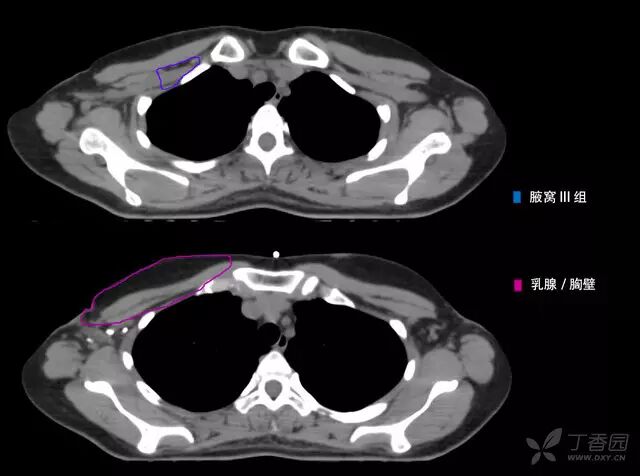

病例 1:左侧乳腺癌术后 t3n3(11/5)m0 iiib 期(下图仅显示锁骨上 ctv